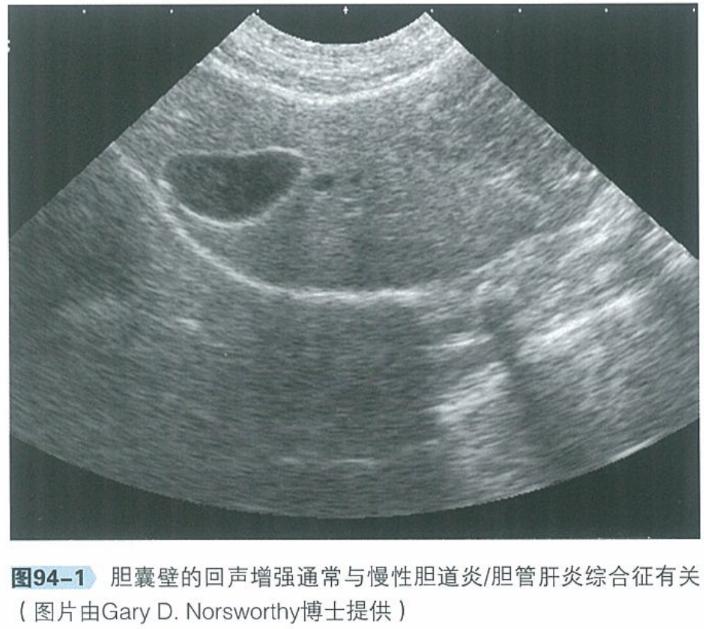

b.腹部超声:腹部超声是检查肝脏、胆管系统及胰腺实质结构极为有用的工具。肝脏回声通常正常,胆管及胆囊可见异常,包括胆总管、胆囊或肝内胆管扩张、部分或完全阻塞,胆汁淤积。

犬猫呕吐的鉴别诊断,犬猫呕吐的诊断和治疗